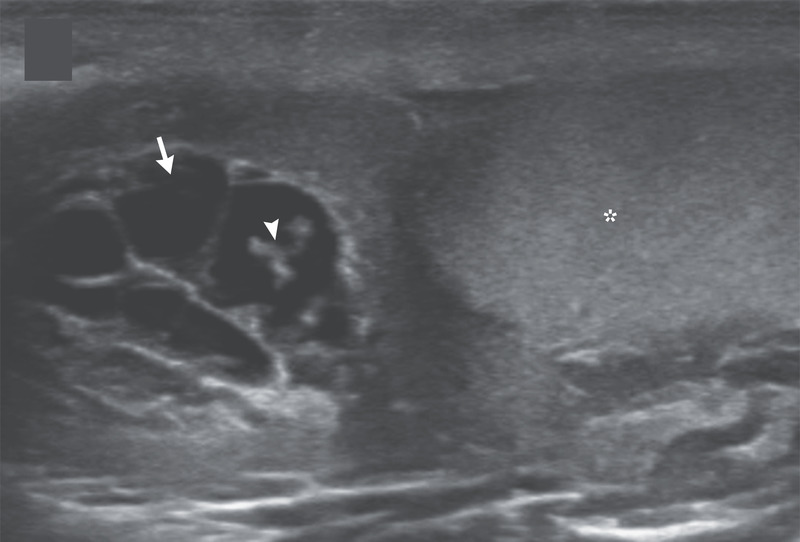

İngiliz Daily Mail gazetesinde yer alan habere göre, doktorlar hastanın skrotumunda hareket eden doğrusal yapılar keşfetti.

Nadir görülen enfeksiyon, New England Journal of Medicine tarafından yayınlanan bir vaka raporu ile ortaya çıktı. Hastayı muayene eden Max Süper Özel Hastanede kıdemli tıbbi danışman olan Dr. Amit Sahu, ultrasonda 'doğrusal yapıların hareket ettiğini' söyledi.

Sahu gözlemledikleri hareket eden doğrusal yapılar için 'dans edecen düzinelerce solucan' ifadesini kullandı. Sahu, 'Lenf sistemine göç ederek kanalların genişlemesine ve işlev bozukluğuna neden oldular' dedi.

Ultrasondan sonra doktorlar skrotumdan sıvı örneği aldı ve mikroskop altında inceledi.